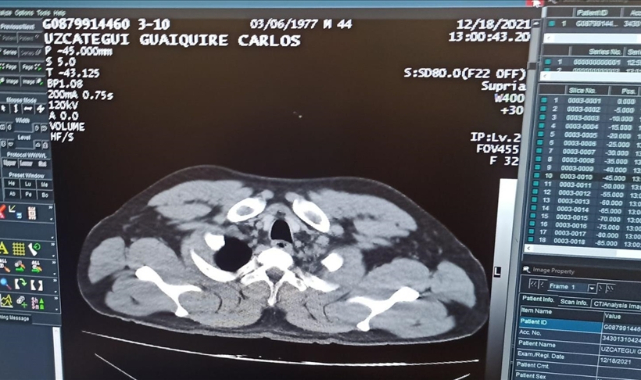

İstanbul Havalimanı'nda rahatsızlanması üzerine kaldırıldığı hastanede mide ve bağırsaklarında 12 kapsül kokain tespit edilen Venezuela uyruklu şüpheli tutuklandı.Yurt dışından geldiği İstanbul Havalimanı'nda 18 Aralık'ta rahatsızlanan yabancı uyruklu bir yolcu, sağlık ekiplerinin ilk müdahalesinin ardından polis kontrolünde hastaneye kaldırıldı.Konuyla ilgili araştırma yapan ekipler, yurt dışından gelen yolcunun Venezuela uyruklu C.M.U.G olduğunu belirledi. Durumundan şüphelenilen yolcu, yapılan mülakatta 12 kapsül şeklinde sarılı kokain yuttuğunu beyan etti.Tomografi kontrolünde de mide ve bağırsaklarda tespit edilen kapsüllerin ameliyatla alındığı şüpheli, taburcu olmasının ardından adliyeye sevk edildi.Şüpheli C.M.U.G, "uyuşturucu madde ticareti yapma" suçundan tutuklandı.

İstanbul Havalimanı'ndaki sağlık ekiplerinin ilk müdahalesinin ardından kaldırıldığı hastanede mide ve bağırsaklarındaki kapsüller ameliyatla alınan Venezuela uyruklu şüpheli tutuklandı.